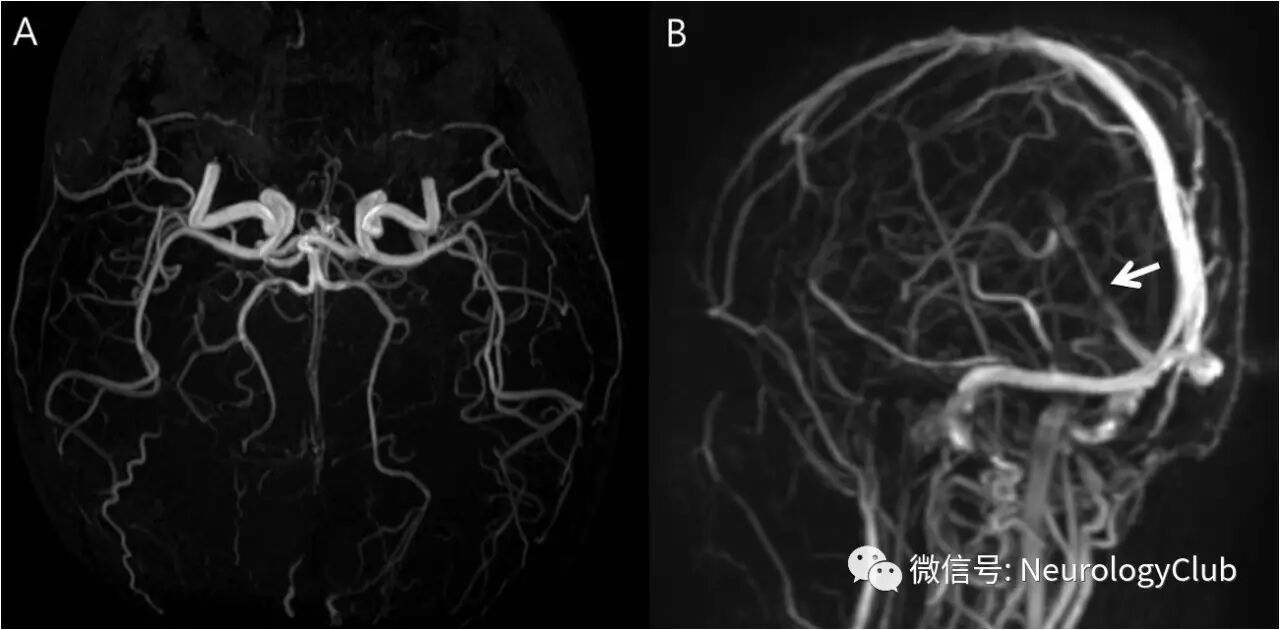

1天后复查DWI,见病灶延伸累及双侧丘脑后部,中脑,脑桥和小脑(图1E-H)。T2WI可见颞枕叶血管源性水肿,梯度回波序列上左侧丘脑,左侧枕叶,中脑,脑桥和左侧小脑(图2A-B)点状出血。此外,梯度回波序列还可见沿着左侧枕叶脑沟的晕状伪影(blooming artifact),符合皮层静脉血栓形成(图2B,箭)。MRA同样未见颅内动脉狭窄或闭塞(图3A)。后一天再复查梯度回波序列可见点状出血进展,MRV上直窦管腔不规整(图3B,箭)。

(图2:A:T2WI可见血管源性水肿;B:梯度回波序列可见点状出血和晕状伪影[箭];C-D:梯度回波序列证实点状出血进展

(图3:A:MRA未见血管狭窄和闭塞;B:MRV可见沿直窦管腔不规整)